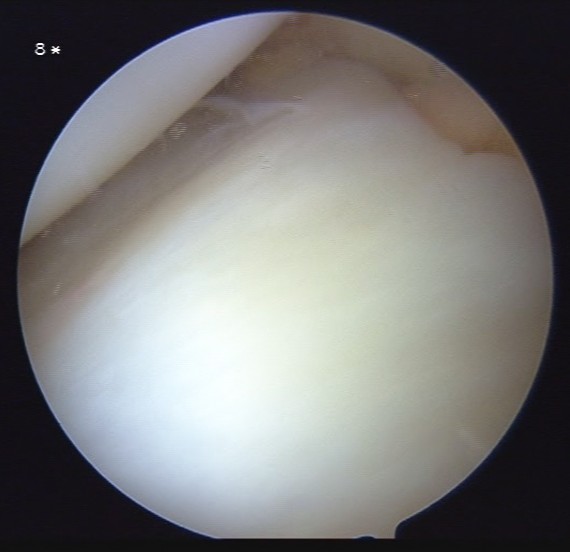

Inside-out repair of the torn meniscus.

A re-look arthroscopy in 3 months’ time showing healed meniscus.